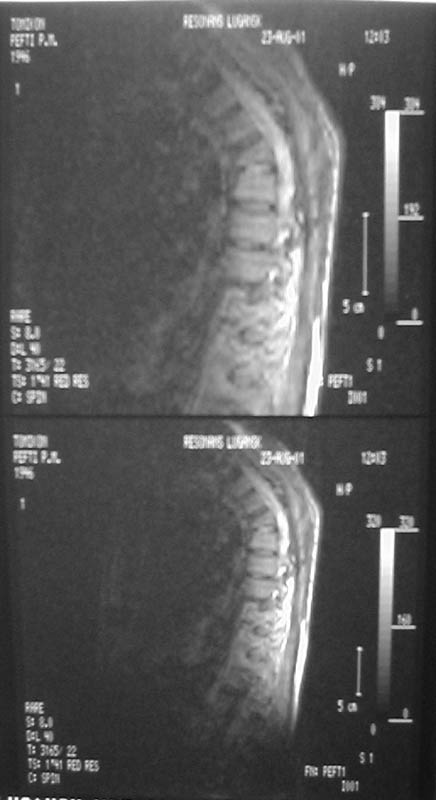

В настоящее время жалобы на отсутствие чувствительности в нижних конечностях, невозможность самостоятельной ходьбы (передвигается на кресле).КОНСУЛЬТАТИВНОЕ ЗАКЛЮЧЕНИЕ ЯМР-ТОМОГРАФИЧЕСКОГО ИССЛЕДОВАНИЯПроведена МР_томография грудного отдела позвоночника в сагиттальной проекции, с различной степенью контрастирования тканей, в режимах Т1 и Т2 В/И + МР-миелоурография. Визуализированы: спинной мозг с уровня D1 до уровня D12, тела позвонков D1-D12, межпозвонковые диски. Спинной мозг на уровне D4-D6 истончен с неровными нечеткими контурами, гетерогенной структуры, умеренно пониженной интенсивности на Т1 В/И, без очаговых изменений. Отмечается клиновидная деформация тела D5, снижена высота тела D4, структура его гетерогенная. Обращают внимание выраженные дегенеративные изменения дисков в грудном отделе позвоночника: снижение их высоты, изменение структуры изображения за счет исчезновения высокоинтенсивного сигнала от ядер. При исследовании в режиме МР-миелоурографии ликворный сигнал на уровне D4-D5 почти прерывается, интенсивность его существенно снижена.

ЗАКЛЮЧЕНИЕ: ПОСЛЕДСТВИЯ КОМПРЕССИОННОГО ПЕРЕЛОМА ТЕЛА D4-D5 С КОМПРЕССИЕЙ СПИННОГО МОЗГА. МРТ-ПРИЗНАКИ МИЕЛОПАТИИ И РУБЦОВО-СПАЕЧНОГО ПРОЦЕССА В ПОЗВОНОЧНОМ КАНАЛЕ НА УРОВНЕ D4-D5. ВЫРАЖЕННЫЕ ДЕГЕРАТИВНЫЕ ИЗМЕНЕНИЯ ДИСКОВ В ГРУДНОМ ОТДЕЛЕ ПОЗВОНОЧНИКА.